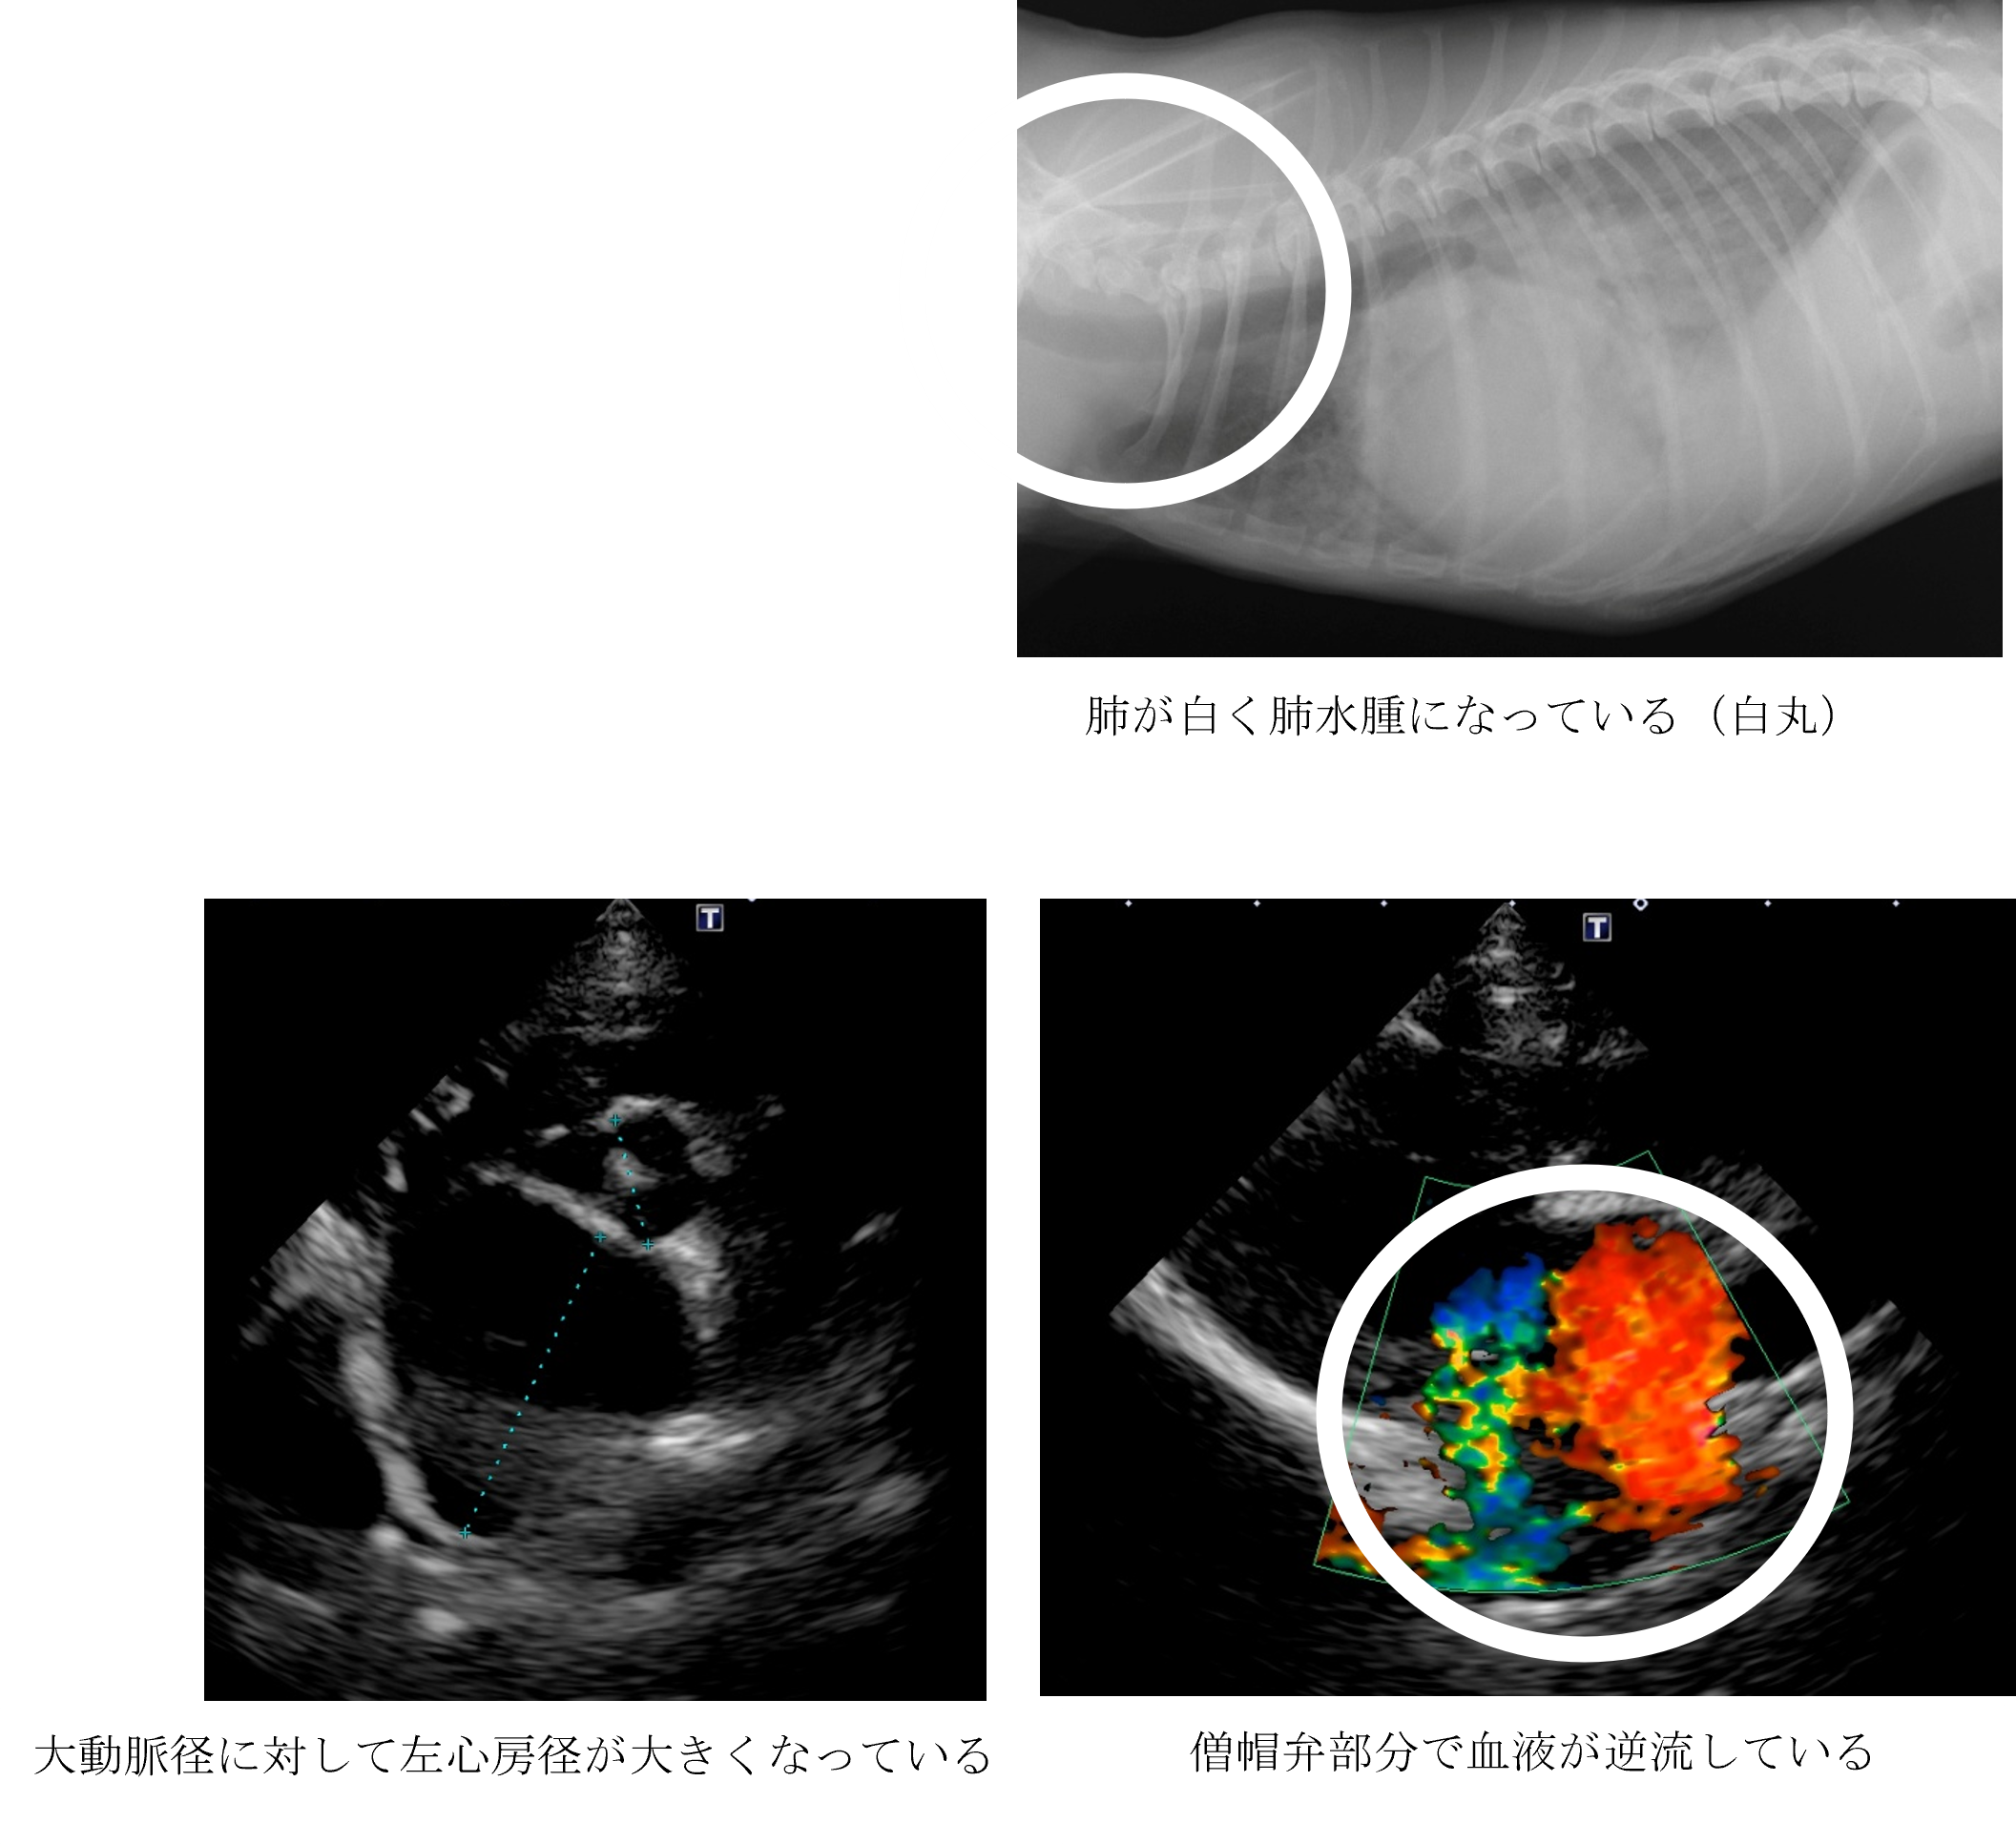

最近散歩に行きたがらなくなり、朝から急に呼吸が苦しい。

各種検査より、僧帽弁閉鎖不全症による肺水腫と診断しました。